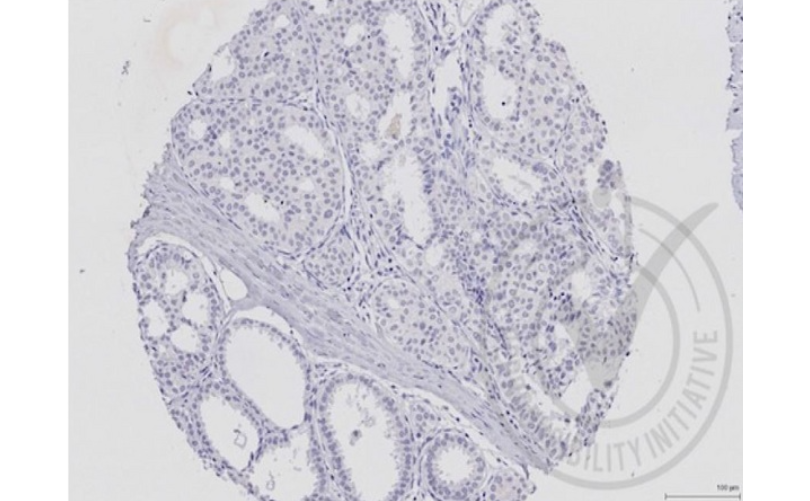

WB, IHC-P, IHC-F, IF, Flow-Cyt, ELISA

Human,Mouse,Rat(predicted:Pig,Cow,Rabbit)